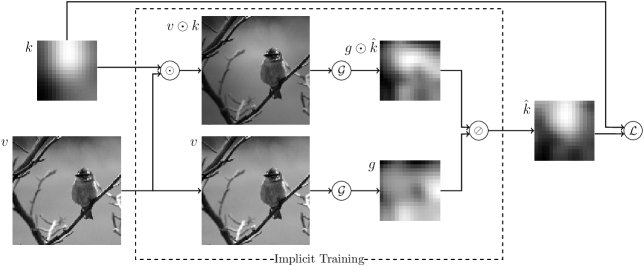

fig:training_pipeline

We used a modified version of ResNet [He et al.(2015)He, Zhang, Ren, and Sun]—that gets us the low-frequency gain field (denoted GetNet) of size from an input image of size , such that

A second network was created that defines what the output of GetNet needs to be (denoted NeedNet). The pipeline for training is illustrated in Figure LABEL:fig:training_pipeline. It uses two instances of GetNet, one fed with the training image and an added gain field , and one fed with only the input . The NeedNet is then defined as

| (3) |

where we note that . Hence, assuming that has similar statistics as , knowing becomes unnecessary, since we can train the network to discard anything that exists on both images. Finally, for training we used the mean absolute error (MAE) loss, , for the number of voxels in .